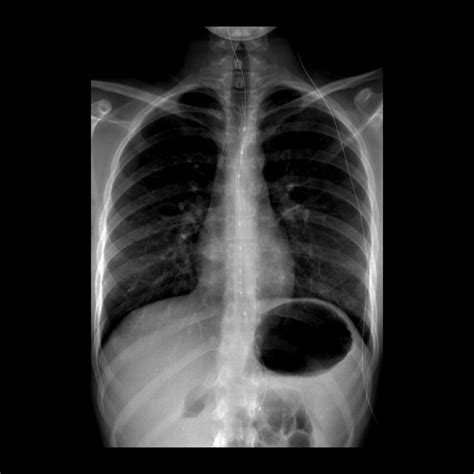

X-Ray Imaging

X-ray imaging is one of the oldest and most widely used diagnosis and imaging techniques. It uses electromagnetic radiation to produce images of the body's internal structures. X-rays are particularly effective for visualizing bones and detecting fractures, as well as identifying certain types of tumors and infections.

Radiation Exposure

Some imaging techniques, such as X-rays and CT scans, use ionizing radiation, which can be harmful if exposure is excessive. Balancing the benefits of these techniques with the risks of radiation exposure is a critical consideration for healthcare providers.